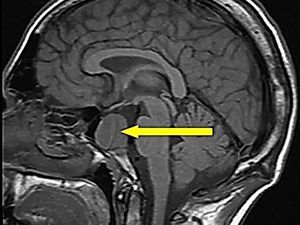

Компьютерная томография гипофиза — это инструментальный рентгенологический метод диагностики, направленный на выявление новообразований этого мозгового придатка.

КТ гипофиза с контрастом в высоком разрешении позволяет сделать исследование максимально эффективным и получить всю необходимую информацию для того, чтобы поставить диагноз и назначить адекватное лечение. Цена КТ гипофиза в клинике ЦЭЛТ представлена на соответствующей странице нашего сайта с прейскурантом услуг. Её можно всегда уточнить, позвонив нам.